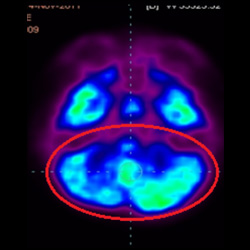

細(xì)胞治療后,藍(lán)色和黑色區(qū)域減少,并且看到更活躍的區(qū)域。這表明損傷減少并改善了大腦功能。

這證明細(xì)胞療法是治療腦癱兒童安全有效的方法。細(xì)胞療法可以更新大腦損傷的核心,并且可以通過 PET CT 掃描來監(jiān)測大腦的改善情況。這些細(xì)胞療法與標(biāo)準(zhǔn)治療一起促進(jìn)腦癱兒童的生長和改善。